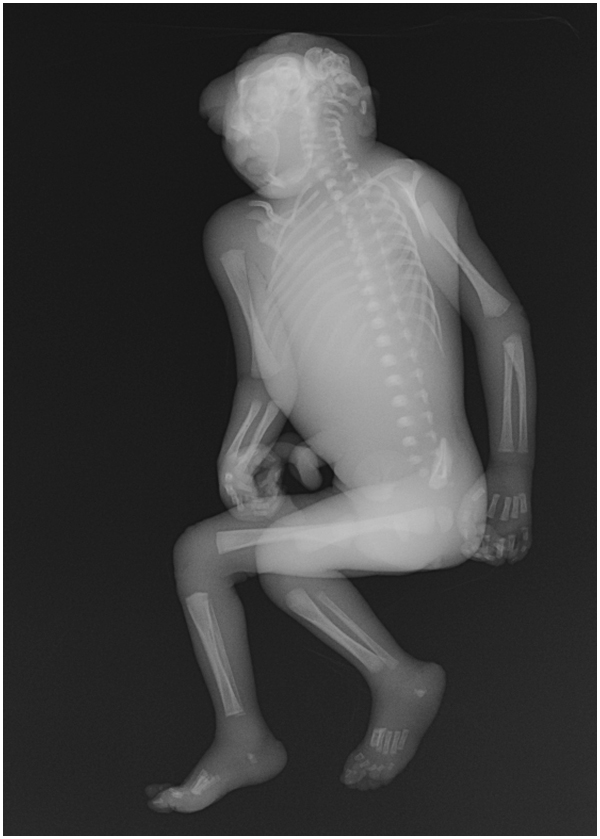

무뇌증은 태아의 신경관이 제대로 닫히지 않아 뇌의 일부분 또는 대부분이 결여되는 선천적 기형이다. 엽산 섭취 부족, 유전적 요인, 특정 약물 복용 등이 원인으로 작용하며, 뇌간을 제외한 대뇌가 형성되지 않아 시각, 청각 상실, 통증 감지 불능 등의 증상을 보인다. 초음파 검사로 진단하며, 치료법은 없고, 예후가 매우 불량하여 대부분 사산되거나 출생 후 단기간 내에 사망한다. 낙태 허용 여부 및 장기 기증과 관련된 윤리적 논쟁이 있으며, 관련 법률이 존재한다.

무뇌증으로 태어난 아기는 대개 시각, 청각을 잃고 주변 환경을 인식하지 못하며 통증을 느끼지 못한다. 뇌간의 일부 기능은 남아있을 수 있어 호흡, 소리나 촉각에 대한 반응과 같은 반사 작용은 나타날 수 있다.[4]

태아의 신경관에서 뇌나 척수가 형성되는 것이 저해되어 뇌의 일부 또는 대부분이 결여되는 질환이다. 대뇌 외에도 생명 유지를 담당하는 뇌간의 발달도 장애를 받으며, 결여되는 경우가 많다. 연수 아랫부분이 존재하면 연하 작용이나 울음을 보이며, 소리 자극, 통각에 반응을 보인다. 원시 반사는 존재하며, 건반사는 항진되어 있다.[43]

머리 부분의 두개골이나 이를 덮는 피부의 일부 또는 전부가 결손되어 뇌가 노출되는 경우도 있으며, 안구 돌출이나 결손, 구순구개열 등도 함께 발생할 수 있다. 노출된 신경은 얇은 막으로 덮여 있으며, 머리카락이나 피부에 연결되어 있다.

메로무뇌증(Meroanencephaly)은 기형 두개골 뼈, 정중 두개골 결손, 그리고 뇌혈관 영역이라고 불리는 두개골 돌출부가 특징이다. 뇌혈관 영역은 단순한 막에서부터 큰 결합 조직 덩어리, 출혈성 혈관, 신경교 결절, 그리고 무질서한 맥락얼기에 이르기까지 다양한 비정상적이고 스펀지 형태의 혈관 조직과 신경교 조직이 혼합된 부위이다.[19]홀로무뇌증(Holoanencephaly)은 뇌간을 제외하고는 뇌가 완전히 형성되지 않는 가장 흔한 유형이다. 홀로무뇌증을 가진 유아는 태어난 후 1일 이상 생존하는 경우가 드물다.[19]

두개척추갈림증(Craniorachischisis)은 뇌혈관구역과 척수혈관구역이 두개골 결손과 척주를 모두 채우는 가장 심각한 유형의 무뇌증이다. 두개골의 덮개가 형성되지 않아 신경 조직이 노출되고 척추에 뼈 결손이 동반되는 특징을 보인다. 두개척추갈림증은 약 1,000번의 출생 중 1번꼴로 발생하지만, 임신 초기에 다양한 물리적 및 화학적 검사로 신경관 폐쇄를 감지할 수 있다.